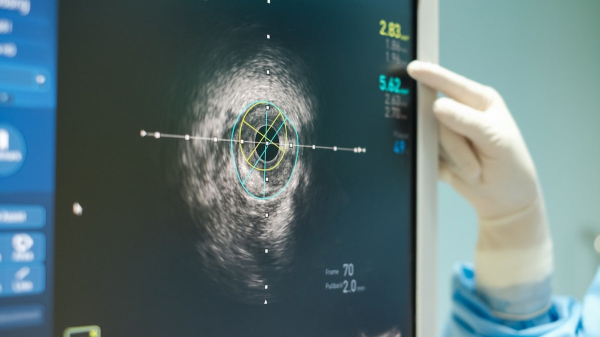

The CAC score is a specialized CT scan that measures calcium buildup in the walls of the heart’s arteries, according to board-certified cardiologist Dr. Robert Segal, founder of Manhattan Cardiology and co-founder of https://www.labfinder.com.

“The CAC score is obtained with a rapid, low-dose CT scan,” Maryland-based Serwer told Fox News Digital.

The scan images are processed using specialized computer software, producing what is called an “Agatston score.”

“This computer algorithm evaluates how much calcium is present and calculates a number or score,” Serwer said.